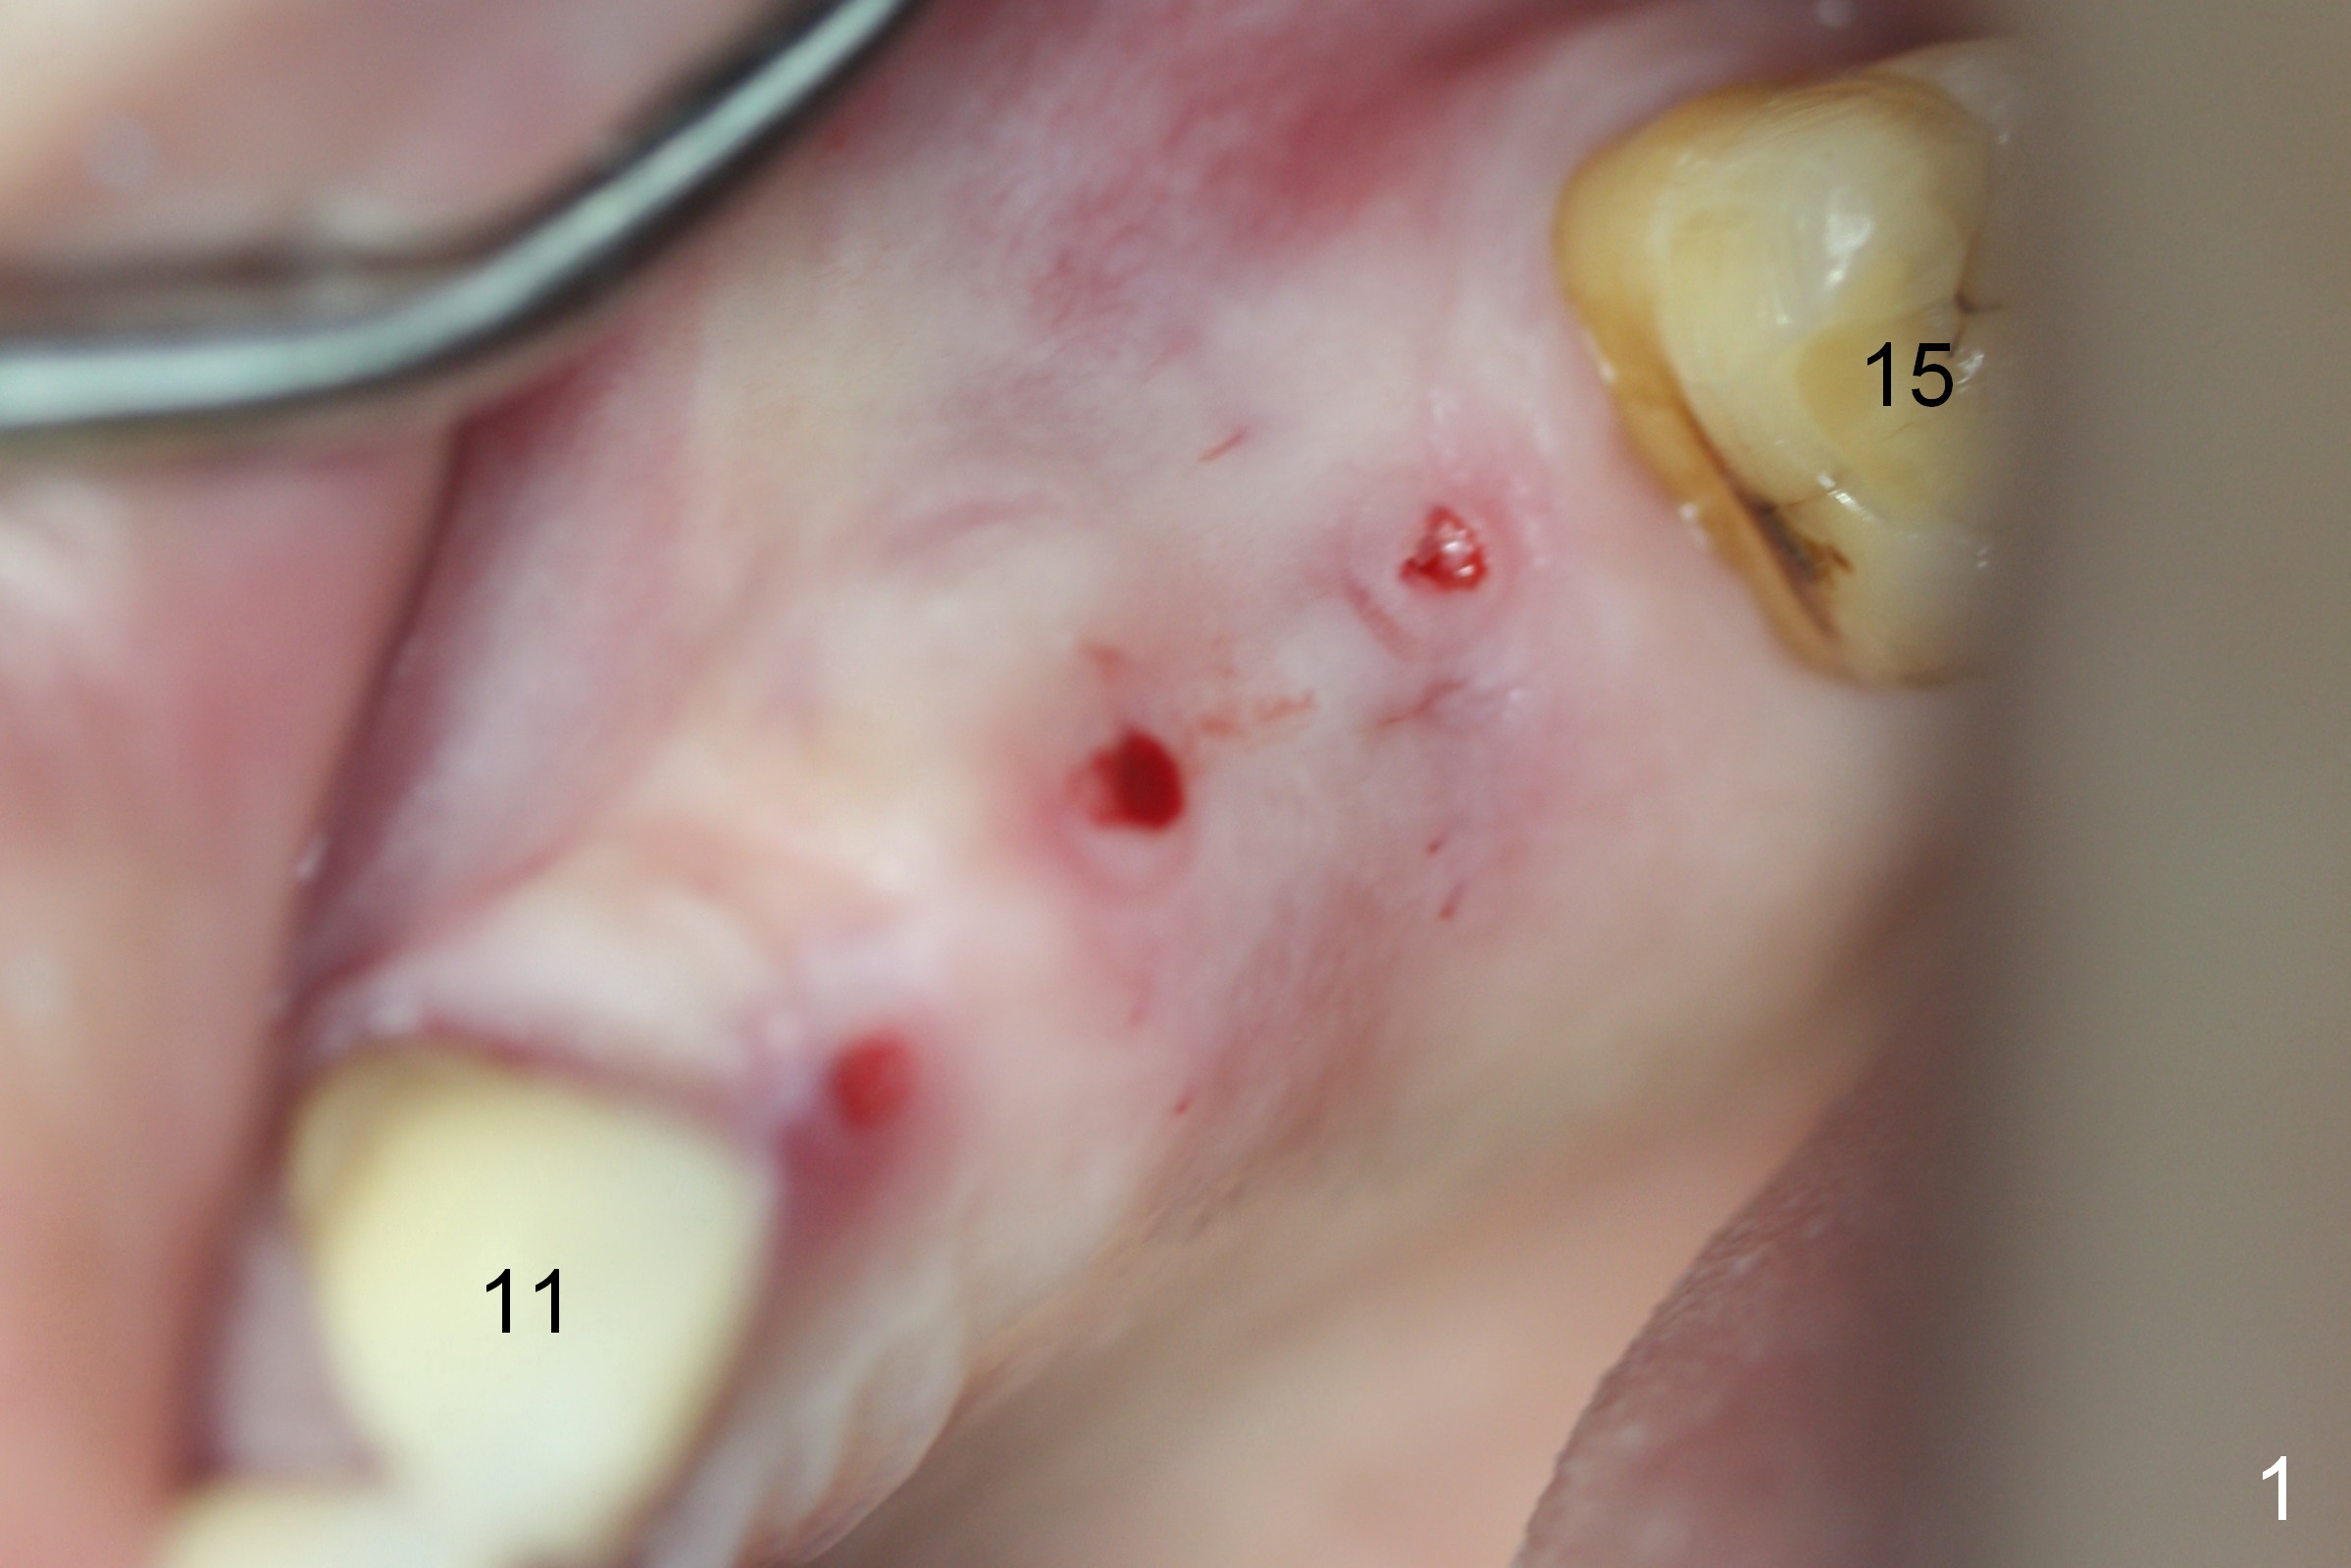

Initial osteotomies are established at the sites of #12-14 through the surgical guide (Fig.1). Following incision, the position of the osteotomies is adjusted buccopalatally where needed. Initial depth is 10 mm (Fig.2); final 14 mm. Ridge split is accomplished between the osteotomies with 7,10 and 13 mm saws from Esset Kit (Hiossen). The osteotomies are enlarged by bone expander drills from the Esset Kit RPM (Fig.3 D). When implants are placed (Fig.4 I (4.1, 3.8 and 5x14 mm)), the gap of split ridge does increase and is subsequently closed by bone graft and membrane. Definitive abutments (A) are installed to hold periodontal dressing in place securely. CBCT study reveals that the bone density between #12-14 are <200 Hounsfield units. When HU is >400, ridge split may result in bone fracture.